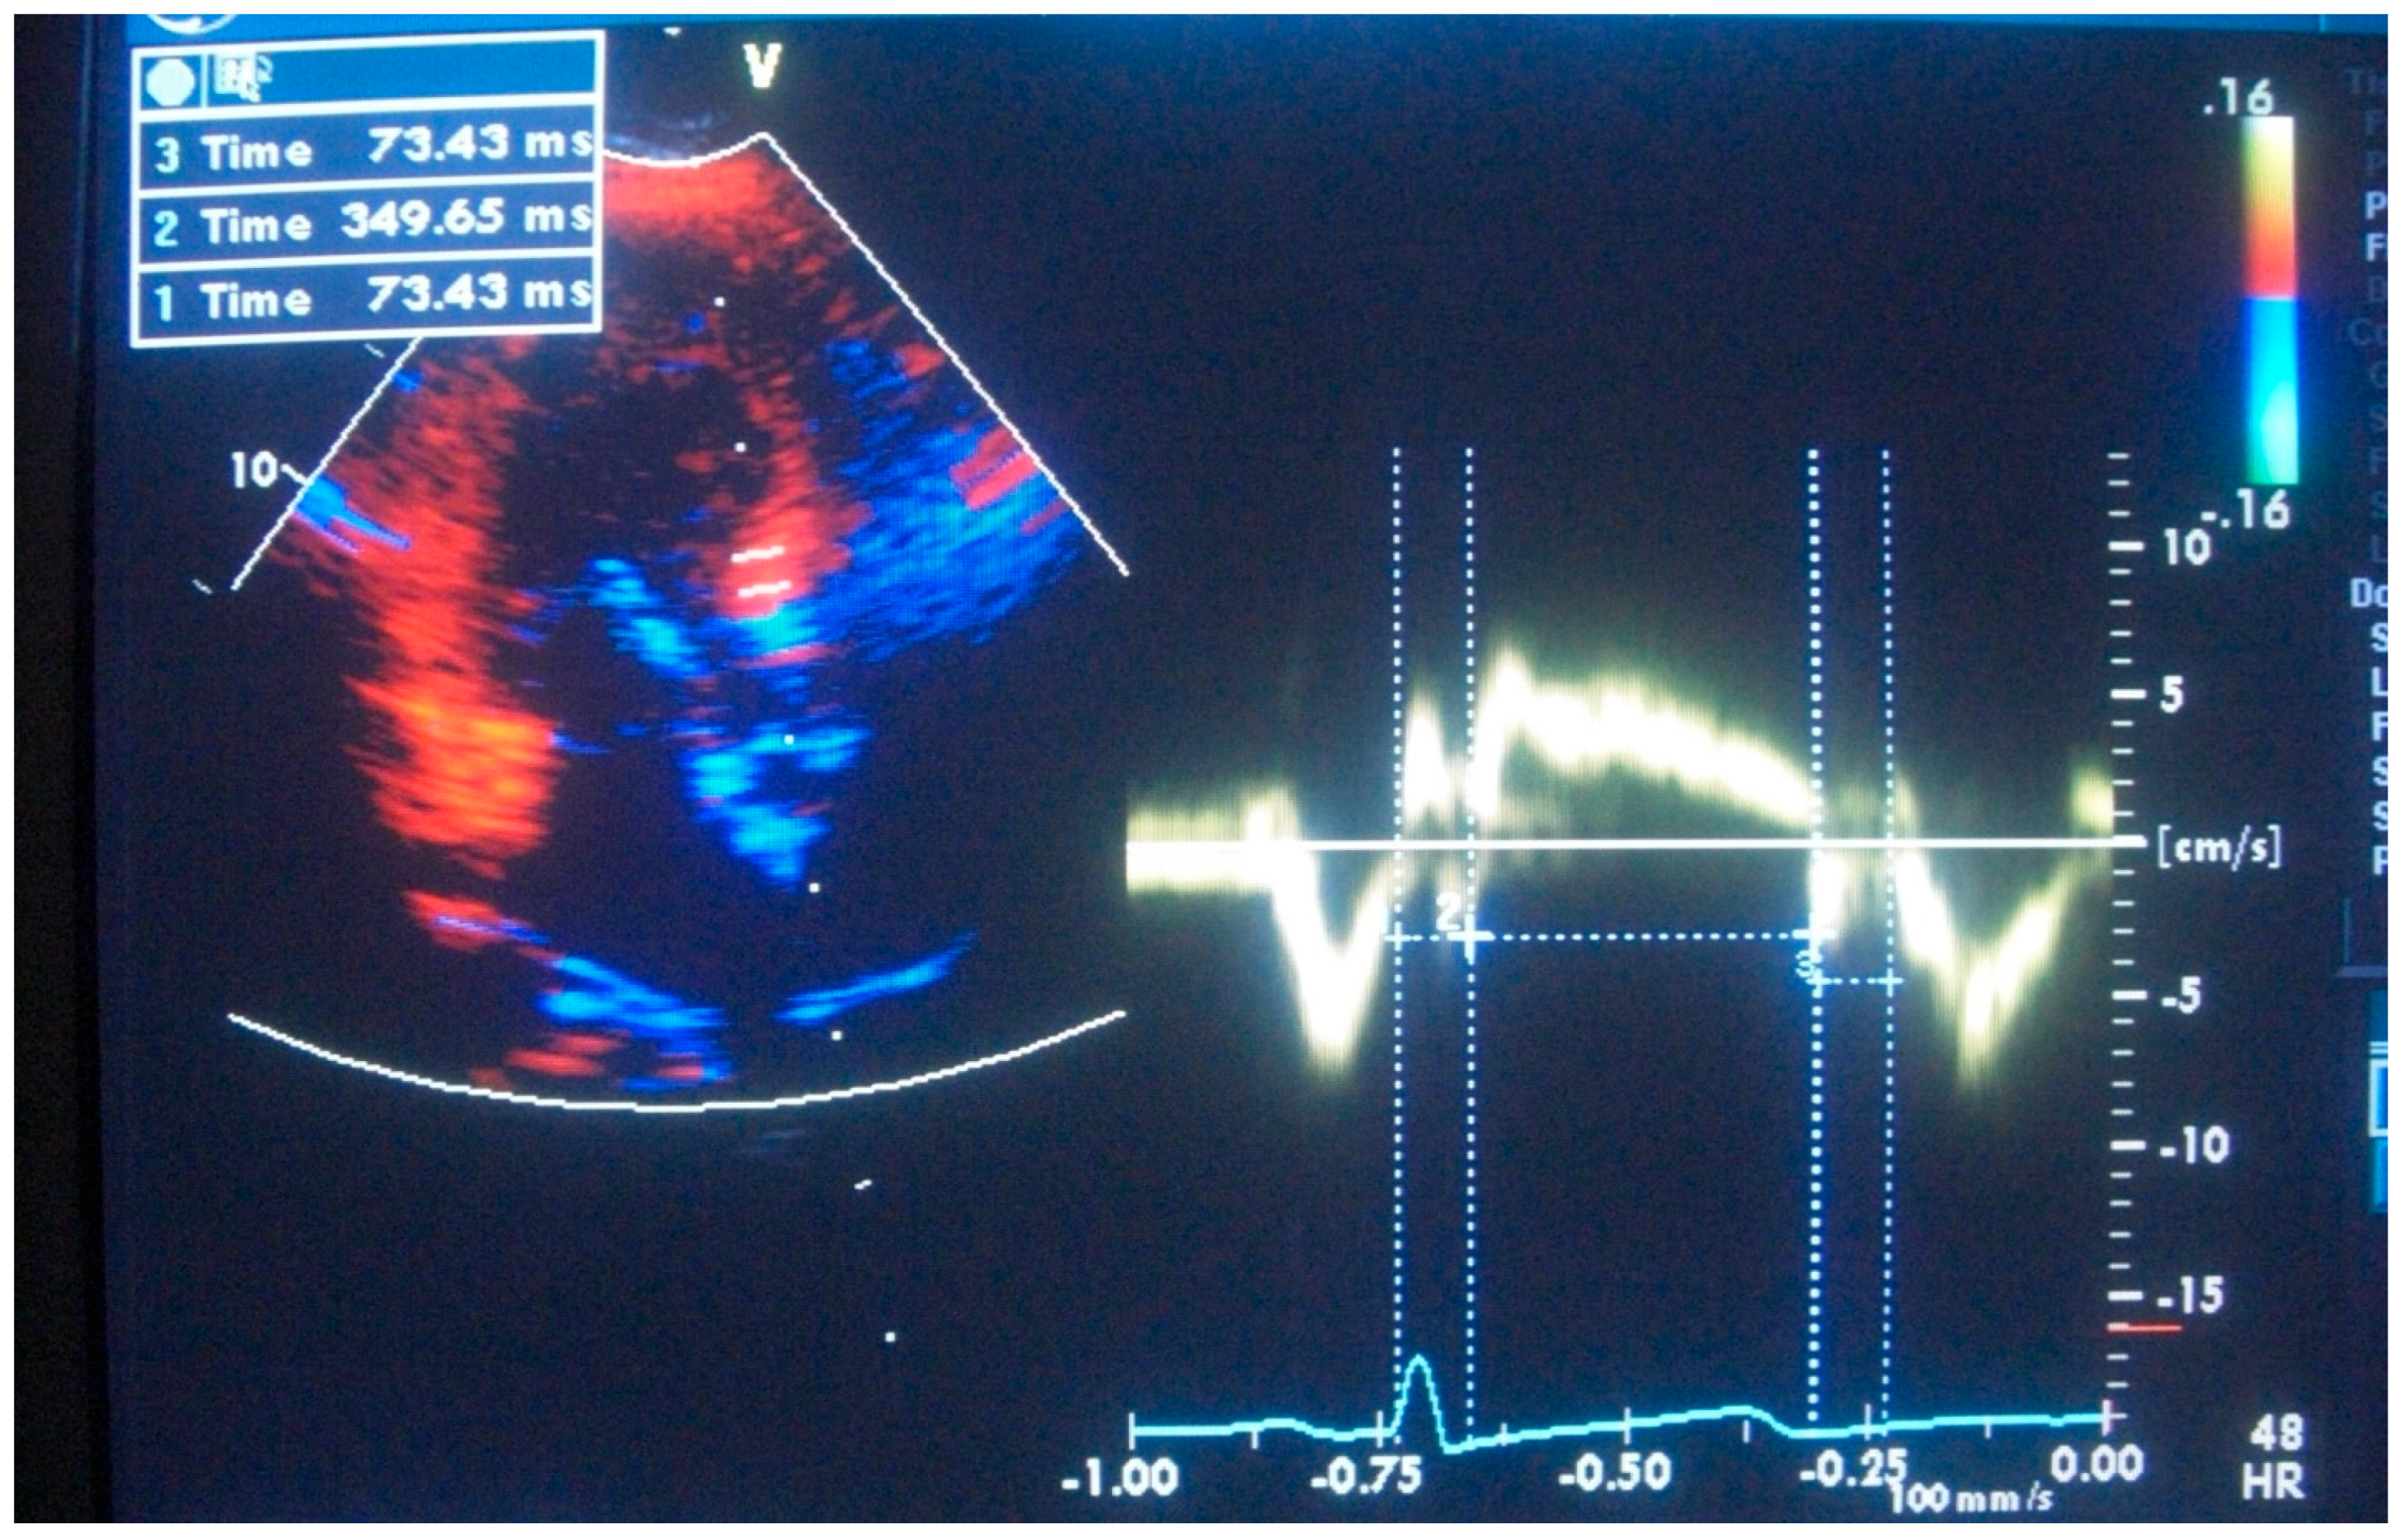

1.4. Segmental Tissue Function of LV Base

- Yalçin, F.; Yiǧit, F.; Erol, T.; Baltali, M.; Korkmaz, M.E.; Müderrisoǧu, H. Effect of Dobutamine Stress on Basal Septal Tissue Dynamics in Hypertensive Patients with Basal Septal Hypertrophy. J. Hum. Hypertens. 2006, 20, 628–630. [Google Scholar] [CrossRef]

- Yalçin, F.; Yalçin, H.; Küçükler, N.; Abraham, T.P. Quantitative Left Ventricular Contractility Analysis under Stress: A New Practical Approach in Follow-up of Hypertensive Patients. J. Hum. Hypertens. 2011, 25, 578–584. [Google Scholar] [CrossRef][Green Version]

- Yalcin, F.; Topaloglu, C.; Kucukler, N.; Yeral, N.; Vefali, H.; Abraham, T.P.; Garcia, M.J. Abstract 11796: Determination of Regional Myocardial Performance in Hypertensive Patients with/without Left Ventricular Hypertrophy. Circulation 2011, 124, A11796. [Google Scholar]